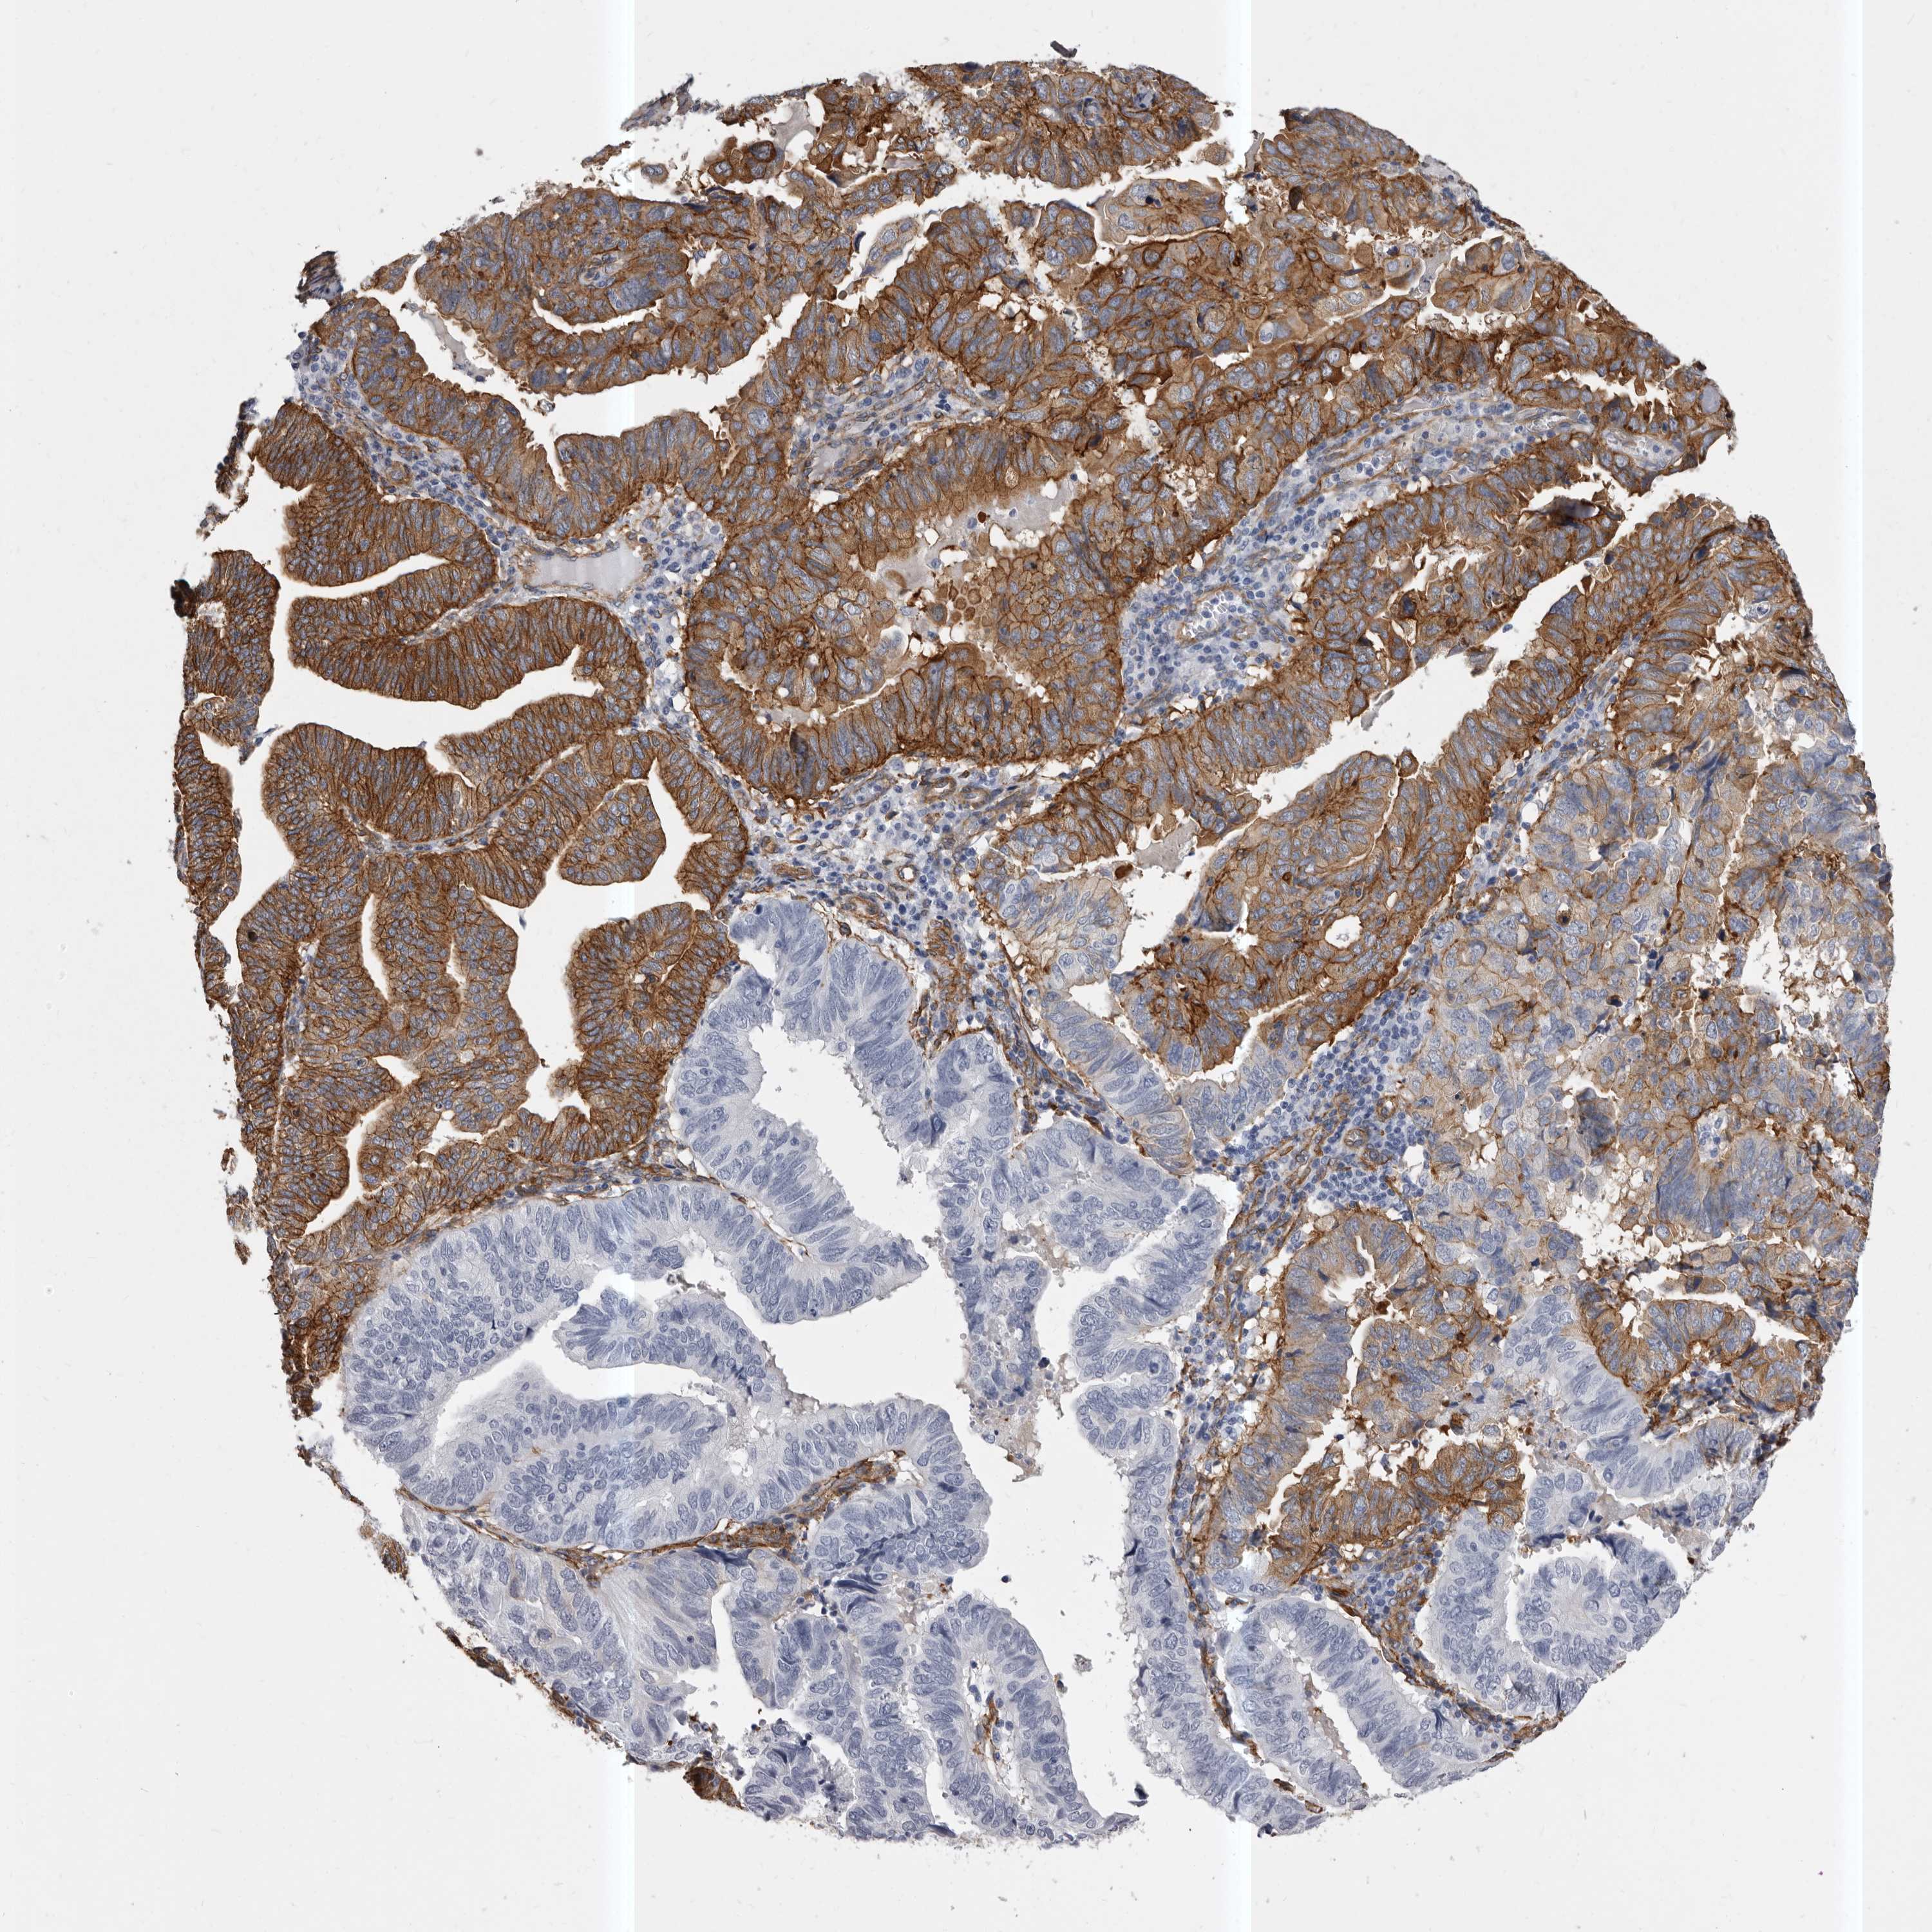

ENDOMETRIAL CANCER - Protein expressioni

A mouse-over function shows sample information and annotation data. Click on an image to view it in a full screen mode. Samples can be filtered based on level of antibody staining by selecting one or several of the following categories: high, medium, low and not detected. The assay and annotation is described here.

Note that samples used for immunohistochemistry by the Human Protein Atlas do not correspond to samples in the TCGA dataset.

Antibody stainingi

Antibody staining in the annotated cell types in the current human tissue is reported as not detected, low, medium, or high, based on conventional immunohistochemistry profiling in selected tissues. This score is based on the combination of the staining intensity and fraction of stained cells.

Each image is clickable and will lead to virtual microscopy that enables deeper exploration of all samples and also displays staining intensity scores, fraction scores and subcellular localization as well as patient and tissue information for each sample.

Antibody HPA028448

Antibody HPA028696

Staining

High

Medium

Low

Not detected

Intensity

Strong

Moderate

Weak

Negative

Quantity

>75%

75%-25%

<25%

None

Location

Nuclear

Cytoplasmic/membranous

Cytoplasmic/membranous,nuclear

Adenocarcinoma, NOS

Adenocarcinoma, metastatic, NOS